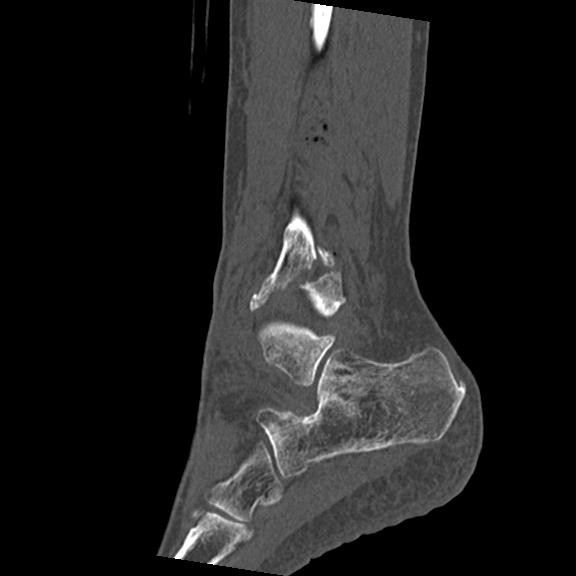

56476 8/28 4R 1/21 2R 左足関節 デジカメ写真 72歳女性 右足関節AS